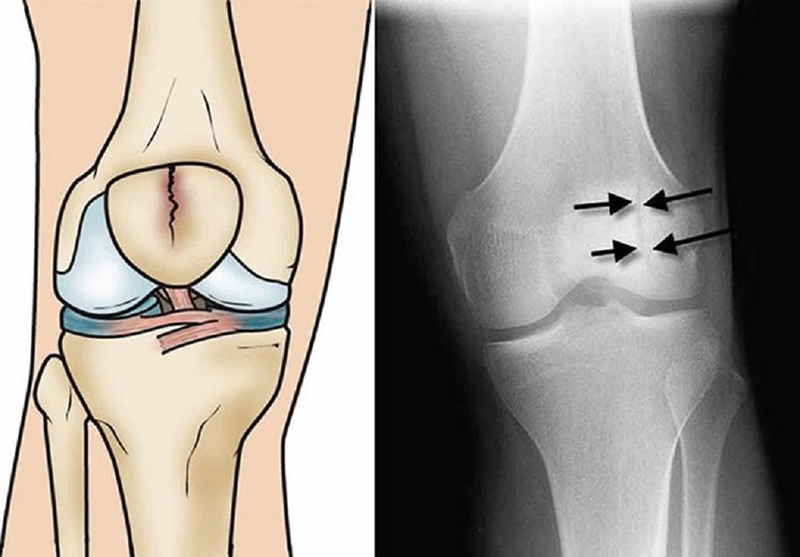

Trước khi tìm hiểu về phẫu thuật kết hợp xương bánh chè, chúng ta hãy đọc qua một số thông tin cơ bản liên quan tới chấn thương ở xương bánh chè. Xương bánh chè đặt ở phía trước của khớp gối, có cấu trúc nhỏ và hình tam giác, nối liền xương chày và xương đùi, đồng thời, mặt sau của nó tiếp xúc trực tiếp với khớp gối.

Khi xương bánh chè đầu gối bị gãy, ảnh hưởng đến cả hệ thống gân và dây chằng tại khớp gối. Trên khía cạnh tính chất của vết thương, vỡ xương bánh chè có thể được phân loại như sau:

Khi xảy ra vỡ xương bánh chè, có thể dẫn đến tổn thương hoặc rách mạch máu xung quanh, gây máu chảy vào khớp. Các biện pháp cấp cứu giúp giảm đau và sưng bằng cách loại bỏ máu và chất lỏng khỏi khớp, tạo điều kiện thuận lợi cho quá trình chẩn đoán.